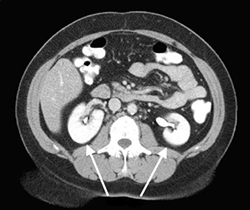

Эта процедура существенно облегчает постановку диагноза. Контрастирование настолько четко визуализирует состояние брюшной полости, что показывает любые изменения в органах. Мультиспиральная КТ − МСКТ почек и надпочечников позволяет быстро и точно диагностировать структурные изменения мочевыделительной системы, представляя послойный снимок исследуемой системы.

КТ может быть проведено с контрастным веществом и без него, связано это с тем, каков предполагаемый диагноз пациента и необходимая степень обследования почек. Т. к. использование контрастирования специальной подготовки организма к процедуре не требует, его могут проводить не только в рамках индивидуализированного лечения, но и во время общего обследования состояния человека.